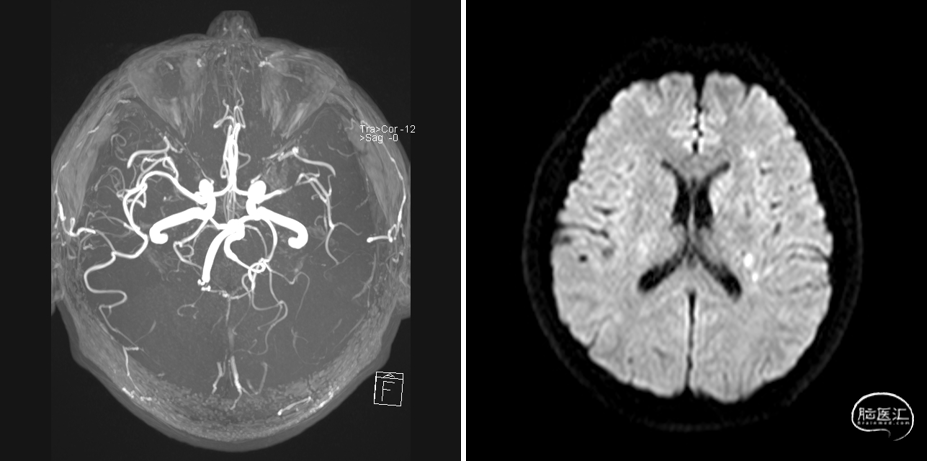

MRA

DWI

重要影像结论:左基底节区、放射冠区脑梗死,左大脑中动脉M1末端狭窄。